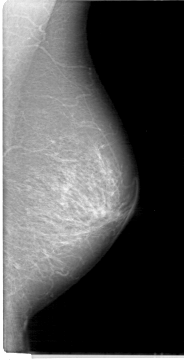

Digital Database for Screening Mammography

Volume: cancer_12 Case: D-4096-1

D_4096_1.LEFT_MLO

LEFT_MLO LINES 5386 PIXELS_PER_LINE 2746 BITS_PER_PIXEL 12 RESOLUTION 43.5 NON_OVERLAY

FILE: D_4096_1.RIGHT_MLO.OVERLAY

TOTAL_ABNORMALITIES 1

ABNORMALITY 1

LESION_TYPE MASS SHAPE OVAL MARGINS OBSCURED

ASSESSMENT 0

SUBTLETY 5

PATHOLOGY MALIGNANT

TOTAL_OUTLINES 1

BOUNDARY